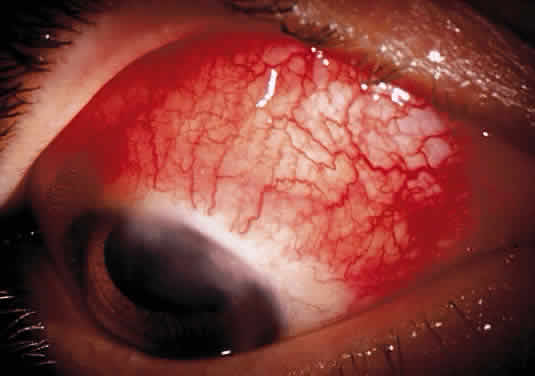

Herpetic keratouveitis can occur in association with any form of herpetic keratitis. Anterior chamber inflammation that accompanies epithelial disease is thought to be caused by reflex irritation and is characteristically both mild and transient. However, the iridocyclitis that invariably accompanies necrotizing disease tends to be much more severe, and is not necessarily correlated with the apparent severity of the keratitis. Indeed, although uveitis dominates the clinical picture in some cases of ocular HSV, subtle corneal findings are limited to faint cellular infiltration of the stroma. Uveitis that accompanies necrotizing disease is typically granulomatous and often recurrent. In more severe cases, perilimbal injection is marked, and the cornea can become thickened and edematous. Dense, fibrinous flare with heavy, anterior chamber cell and medium-sized white keratic precipitates may be distributed widely over the endothelium (Fig. 2). A hypopyon and synechiae can form, and elevated intraocular pressure that exacerbates this often painful uveitis may develop. Marked dilation of iris blood vessels and spontaneous hyphemas sometimes occur. Episodes of inflammation are frequently marked by progressive iris atrophy and sphincter damage, leading to corectopia and anisocoria (Figs. 3 and 4).